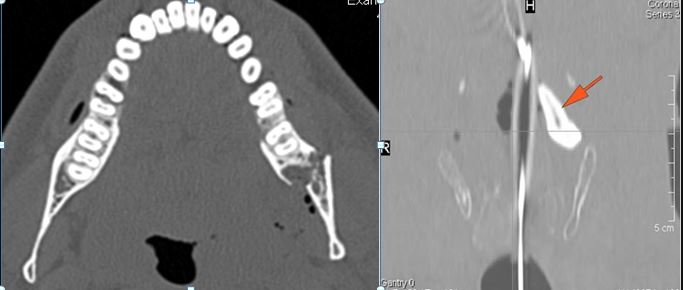

34-year-old male in the ER following an altercation with possible mandibular or other facial fractures due to craniofacial trauma.Exam

34-year-old male in the ER following an altercation with possible mandibular or other facial fractures due to craniofacial trauma.